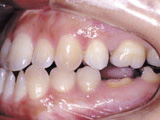

症例1:乱杭歯「歯並びが乱れている」

治療前

治療後